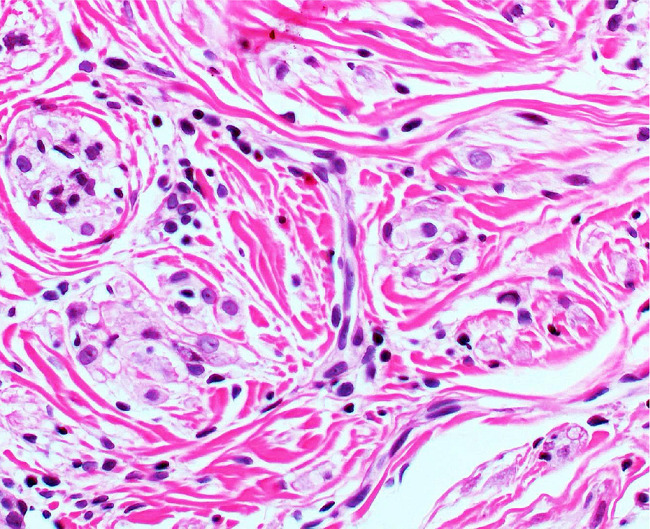

O anatomopatológico apresentou lesão dérmica composta por células fusiformes/ovaladas dispostas aleatoriamente com estroma colagenizado, áreas de aprisionamento de colágeno na periferia, proliferação capilar de permeio e raras figuras de mitose (Figura 2).

O diagnóstico diferencial dos NTs é diverso e inclui neoplasias benignas, malignas e inflamatórias. A histologia é padrão-ouro para diagnóstico e é caracterizada pela presença de lesão dérmica circunscrita e lobular. Predominam ninhos de células epitelioides ou células tumorais em sutil padrão espiralado. Abundantes citoplasmas granulares eosinofílicos, com núcleos redondos ou ovais, são observados.1,3